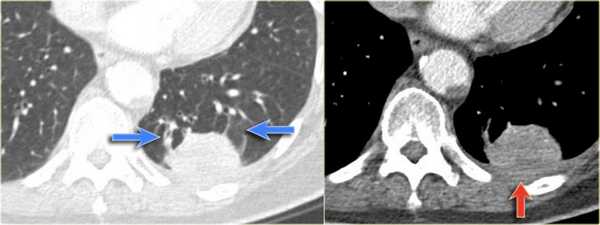

На КТ снимках синей стрелкой указан долевой ателектаз, а красной стрелкой опухоль, которая обтурирует левый верхний долевой бронх (центральный рак легкого.

Ателектаз верхней доли левого легкого с типичным симптомом воздушного серпа (Luftsichel sign — luft(air)+sichel(sickle)), обусловленный гипервентиляцией верхнего сегмента нижней доли левого легкого на фоне коллапса верхний доли левого легкого. Гипервентилируемый

сегмент визуализируется на прямой рентгенограмме от дуги аорты до апикальной части легкого.

На ниже представленной рентгенограмме пациента с карциноматозом плевры левое легкое полностью компрессируется плевральной жидкостью (левый гемоторакс). В выше представленных случаях был обтурационный ателектаз, а в этом компрессионный, что лучше визуализируется на КТ (синяя стрелка). КТ данному пациенту также проводили по причине легочного эмболизма (красная стрелка).

На КТ четко выявлено, что это образование легкого. Для многих данные изменения на КТ заставили бы задуматься о раке легкого. Красной стрелкой указана утолщение плевры, а синими стрелками указаны сосуды вокруг данного образования, что называют хвостом кометы.